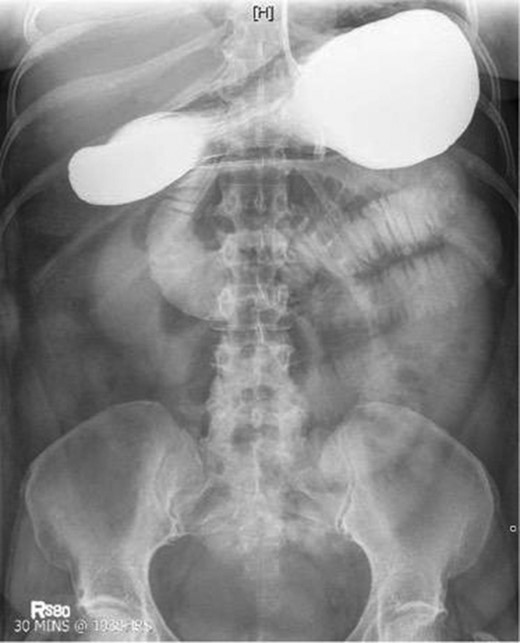

Laboratory studies were remarkable for leukocytosis, and an elevated lactate that improved with hydration (Fig. 1), while urinalysis was unremarkable. Abdominal CT scan obtained at this time demonstrated a partial SBO in the mid-small bowel as well as inflammation and thickening of the duodenum. A small bowel series was ordered, and showed high grade SBO (Figs 2–5).

Fluoroscopic barium study demonstrating oral contrast agent progression through the small bowel at 1 h after ingestion. The stomach is distended, with dilated bowel loops throughout the abdomen.